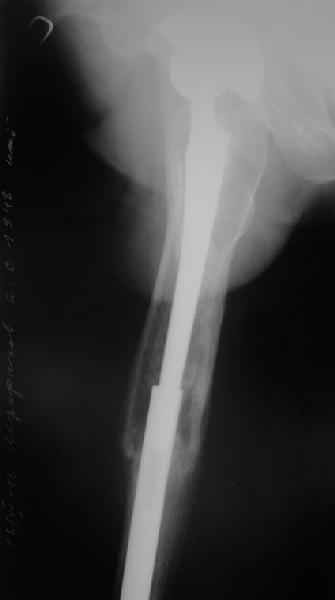

Перелом бедра сросся. Конечность опорная и безболезненная, ходит без трости. Ножка, похоже, реинтегрировалась, как и надеялись. Снимки и фото в приложении. Комментарии приветствуются.

Надо ли что-то делать дальше, как полагаете? Убрать винты? Убрать "удлинитель ножки"? Или оставить все, как есть? Спасибо заранее.